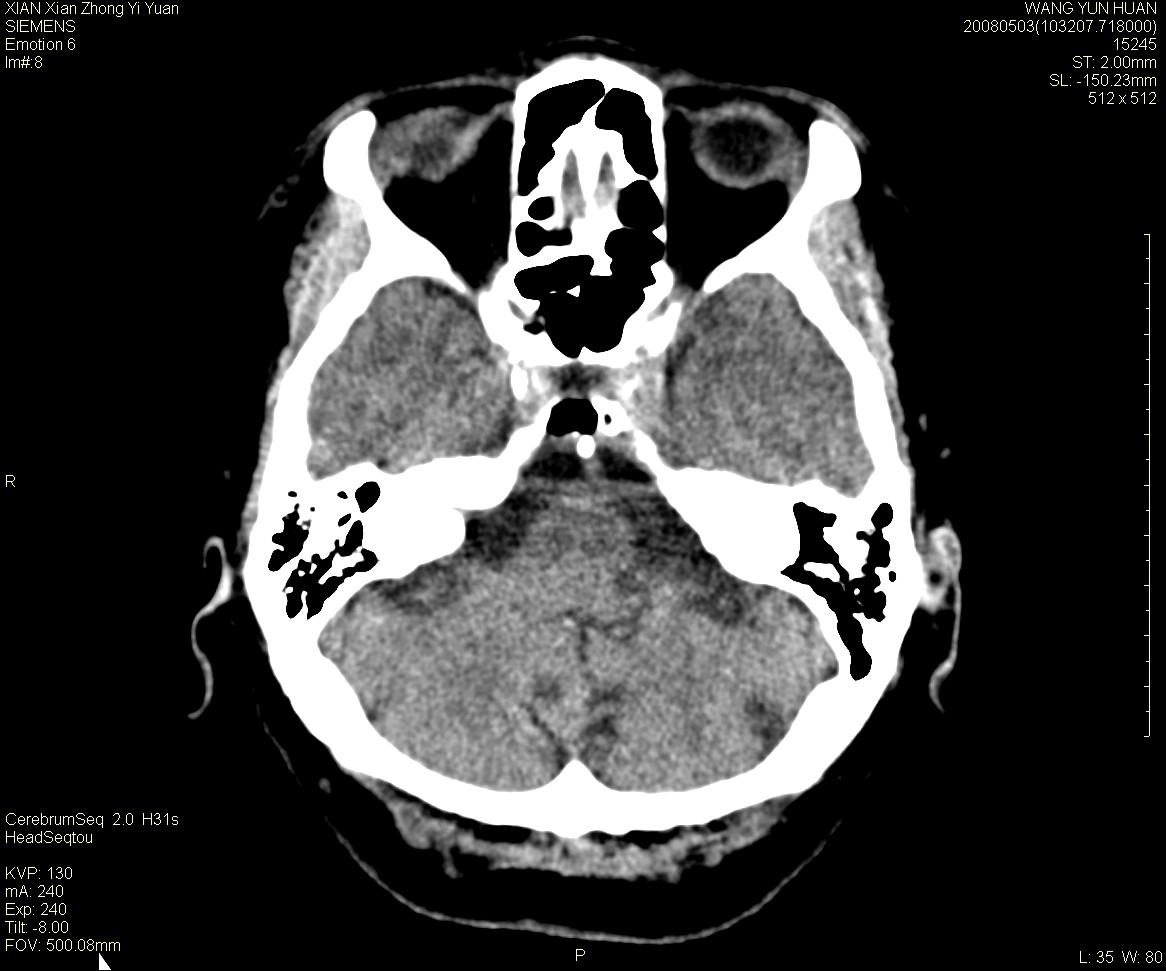

标题: CT13219:(补充强化)请会诊,患者女,60岁,头晕,大家看 [打印本页]

标题: CT13219:(补充强化)请会诊,患者女,60岁,头晕,大家看

病灶显示轻度强化,ct增加4hu左右,大家看是什么肿瘤.

强化后动脉期及延迟2分钟,五分钟图像